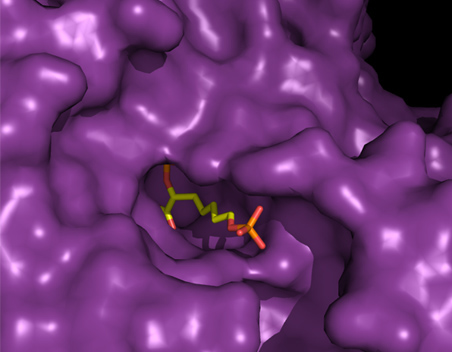

New anti-viral based therapies for Covid-19: Protease inhibitors

Researchers at MWC are looking to develop novel inhibitors for SARS-CoV-2 Mpro by leveraging expertise within MWC’s Infectious Disease network for anti-viral drug development.

Smarter drug design

An advanced experimental technique linked to high powered computation is becoming an increasingly important tool for MWC researchers developing new drugs.

Early career researchers zoom in on an important drug target

An estimated 1.3 million people die from tuberculosis (TB) each year, and new drugs are desperately needed, especially as resistance to existing drugs increases.